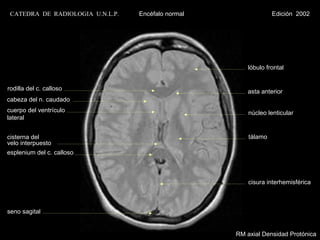

lóbulo frontal

rodilla del c. calloso                                 asta anterior

cabeza del n. caudado

cuerpo del ventrículo                                   núcleo lenticular

lateral

cisterna del                                            tálamo

velo interpuesto

esplenium del c. calloso

cisura interhemisférica

seno sagital

RM axial Densidad Protónica